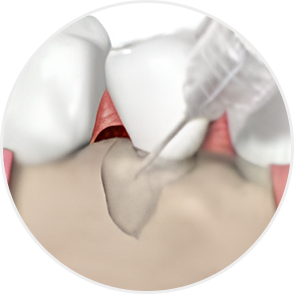

Emdogain Surgical Procedure

STEP 01

Gingival incision

-

STEP 02

Scaling and Root Planing (SRP)

STEP 03

Removal of calculus and plaque

STEP 04

Emdogain application

STEP 05

Cleansing

STEP 06

Flap closure and suturing